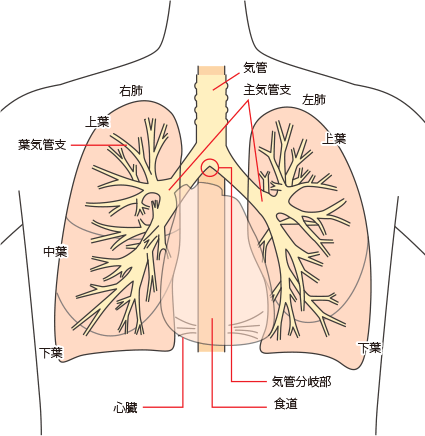

覚えておきたい、肺の構造と名称

胸の中の構造

肺がんは、さまざまな検査を受けたり、長い時間をかけて治療をしなければならない病気です。 検査や治療をすすめていくにあたっては、主治医から十分な説明を受けて、それをよく理解したうえで同意することが大切です。主治医の話を聞く前に、肺がんの基礎知識として、治療法の選択基準となる肺がんの種類・肺がんの大きさと広がりについて知っておきましょう。

胸の中の構造を確認する

肺がんでは、肺門(肺の入り口周辺)リンパ節、肺内(肺の中)リンパ節、縦隔(左右の肺に挟まれた空間)リンパ節という3つのグループに分かれます。